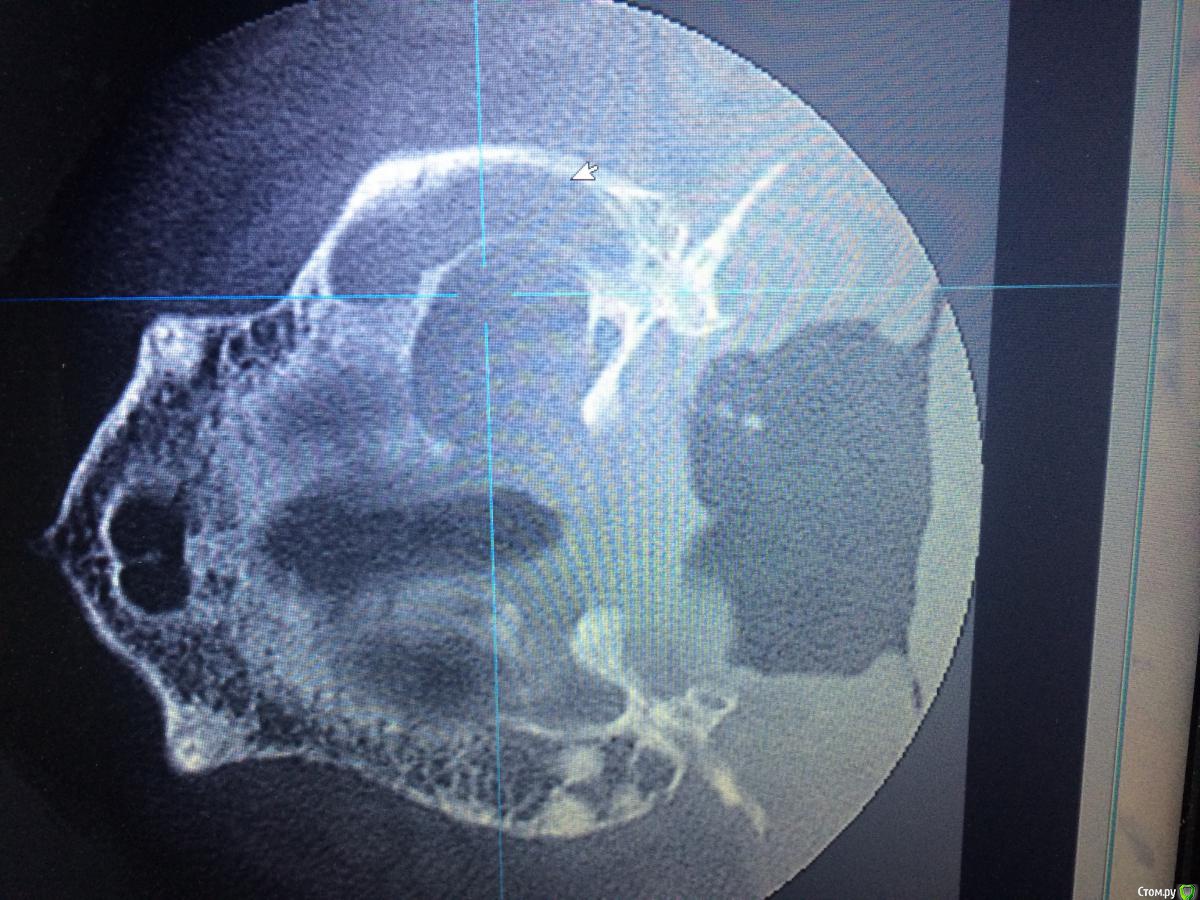

Shargik Опубликовано 23 октября, 2015 Поделиться Опубликовано 23 октября, 2015 Господа эндодонтисты, вот Вам такой случай.. Как думаете, стоит с ним повоевать, или сразу в плевашку? Беспокоит выбухание на небе и свищ с непрекращающимся гноетечением, каналы все проходимы, вот думаю, что с ним делать. Кто прилагается.. Ссылка на комментарий

Evikrol Опубликовано 23 октября, 2015 Поделиться Опубликовано 23 октября, 2015 Воокруг нёбного корня никакой костной поддержки. Я за плевашку Ссылка на комментарий

Shargik Опубликовано 23 октября, 2015 Автор Поделиться Опубликовано 23 октября, 2015 Зуб 26, на небном корне обширный процесс. С небной стороны кости нет от слова совсем. В том то и дело, что пациент не сильно платёжеспособен, думается мне попробовать полечить, авось косточки хоть чуть вырастет, или думаете, это с мельницами бодаться.. Ссылка на комментарий